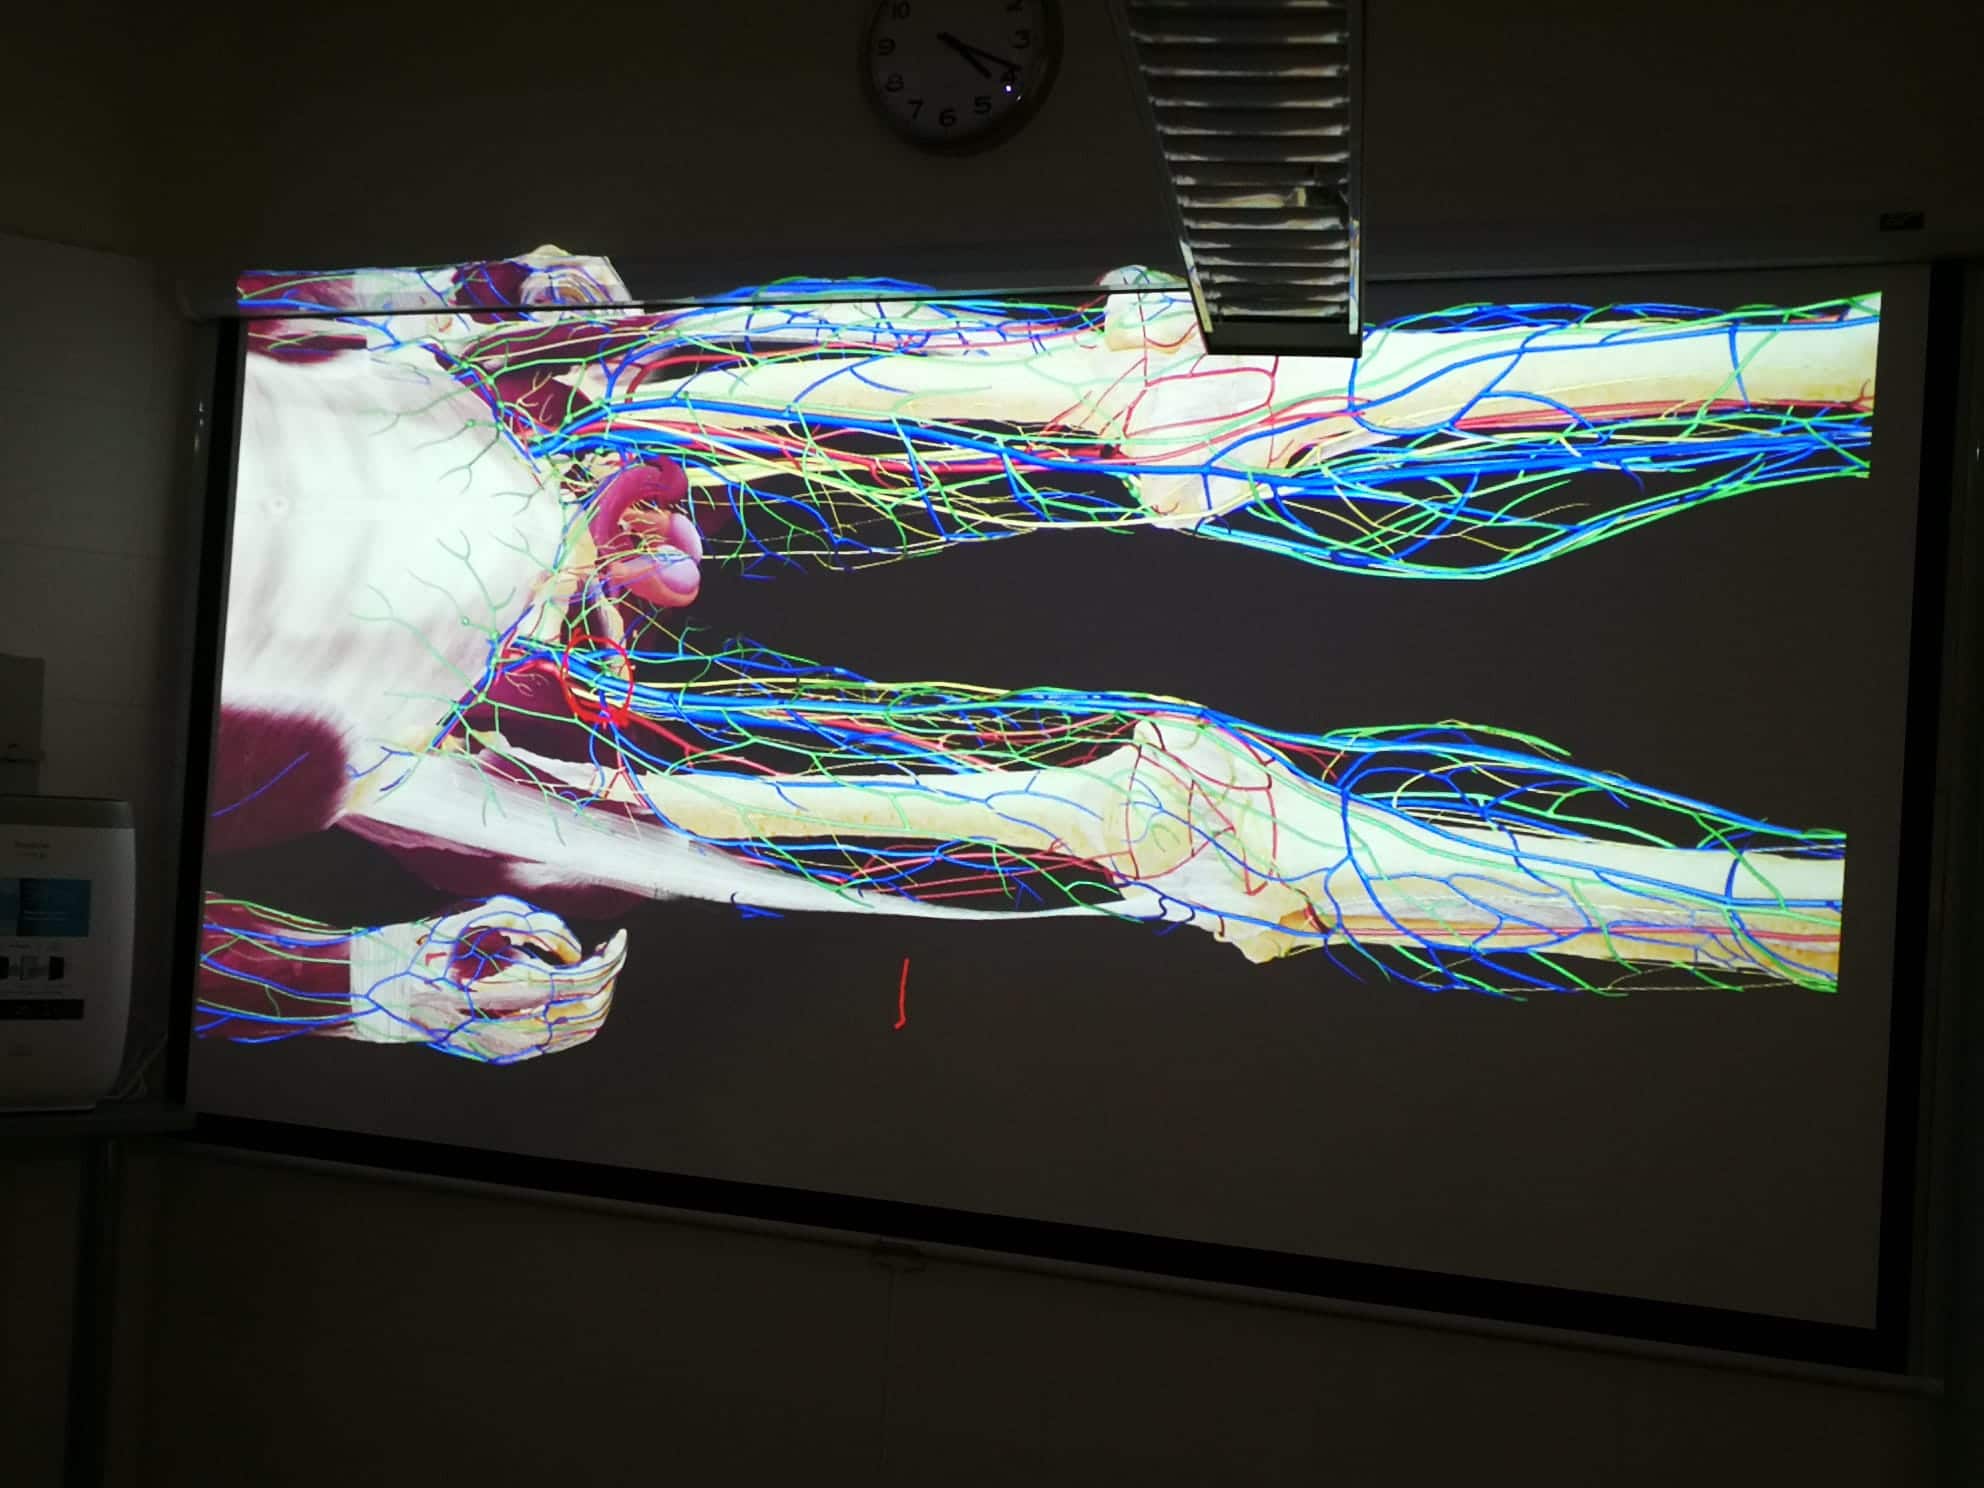

LUGAR: Av. de los Jerónimos, 135, 30107 Guadalupe (Murcia) – Sala de disección de la UCAM (Aulario 6)

DURACIÓN: 20 Horas

DOCENTES: Antonio García Godino, Manuel Moreno Más, Jose María Belmonte Hernández y Andrés Martínez Almagro

DIRIGIDO A: Fisioterapeutas y alumnos de fisioterapia